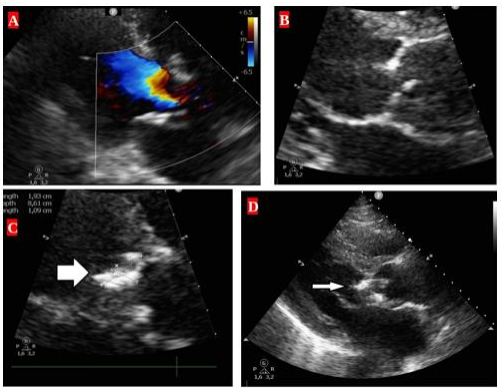

Figure 1:A. Significant aortic regurigitation (colour Doppler ultrasound picture). B. Significant aortic regurigitation. C. D. Visible vegetation on the aortic valve.On the fourth week post operation, the patient developed high-grade septic fever (up to 39.5°C). Laboratory testing excluded HIV, HBV, HCV, EBV, and CMV infection. Blood and urine cultures were repeatedly sterile. Echocardiography revealed no new vegetations, in line with Duke criteria assessment [3]. The site of temporary pacing lead insertion appeared unremarkable.